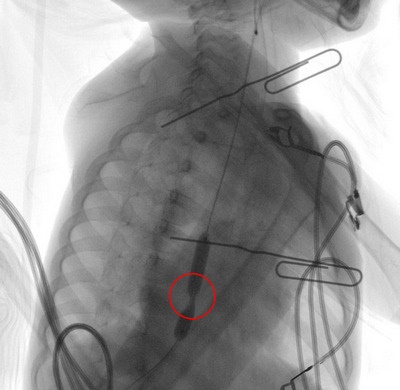

▲執行氣球擴張術過程中,紅色圈起處為食道下段狹窄部位。